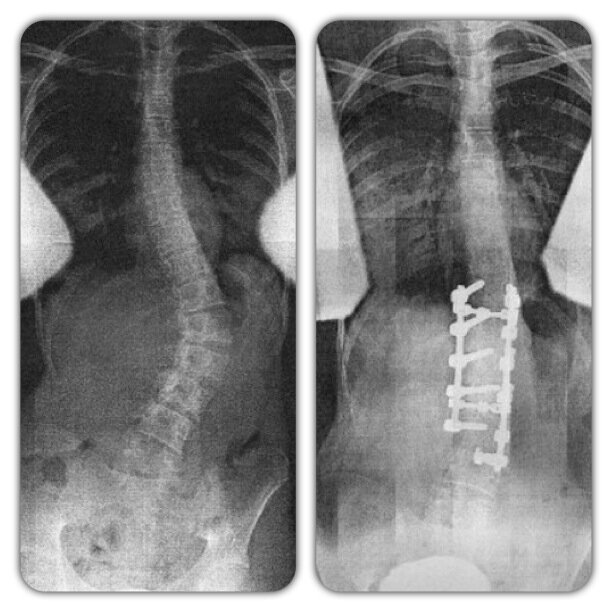

4/2/13•People always ask me,if it hurts why keep cheering.It's because I've fallen to in love with this sport.• It's ok to be different •Cheering with a twist • ask.fm/TwistedCheer Scoliosis Strong Joined April 2013-

139 Followers 133 Following Fusion 6/30/09.. In 6 hours I grew 2 inches and went from 54 to 18 degrees (: instagram: jrodslilsis